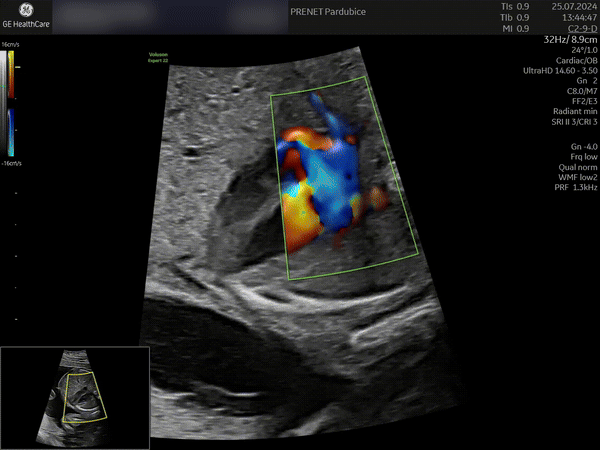

Naše klinika prenatální péče a genetiky nově disponuje nejvýkonnějším ultrazvukovým přístrojem na trhu –Voluson™ Expert 22 od GE Healthcare. Špičkový systém přináší zcela nový standard v oblasti prenatální diagnostiky.

„VolusonTM Expert 22 je přístrojem, který disponuje nejmodernějšími technologiemi pro zobrazování plodu ultrazvukem. Vysoká kvalita obrazu zaručuje mimořádně detailní a přesné zobrazení jednotlivých struktur plodu včetně jeho cévního zásobení. Tyto parametry nejen že zvyšují přesnost naší diagnostiky, ale hlavně posouvají naše možnosti záchytu vrozených vad do časnějších fází těhotenství. Kvalitní 3D/4D technologie zaručuje precizní posouzení prostorových vztahů. Bez její dostupnosti si dnes například nedokážeme představit cílené vyšetření mozku plodu a významně nám dokáže pomoci i v upřesnění celé řady dalších abnormálních nálezů. Takovéto přístrojové vybavení vnímáme jako nepodkročitelnou podmínku pro poskytování prenatální diagnostiky a té nejvyšší možné úrovni, “ prof. MUDr. Ivana Kacerovská Musilová, Ph.D. Odborný garant a gynekolog

„Jako první a dosud jediné zdravotnické zařízení v Pardubickém kraji můžeme našim klientkám nabídnout diagnostiku pomocí této špičkové technologie, kterou dosud využívají v ČR pouze jednotky specializovaných center. Díky Voluson™ Expert 22 jsme schopni detekovat i velmi diskrétní vady, které mnohdy může být velmi složité zobrazit na starších technologiích, dále tím zvyšujeme přesnost diagnostiky plodu. Naše pacientky mají jistotu, že dostávají tu nejlepší možnou péči s využitím nejmodernějších technologií dostupných v oblasti prenatální medicíny, “ dodává Ing. Ondřej Michalovský, výkonný ředitel společnosti